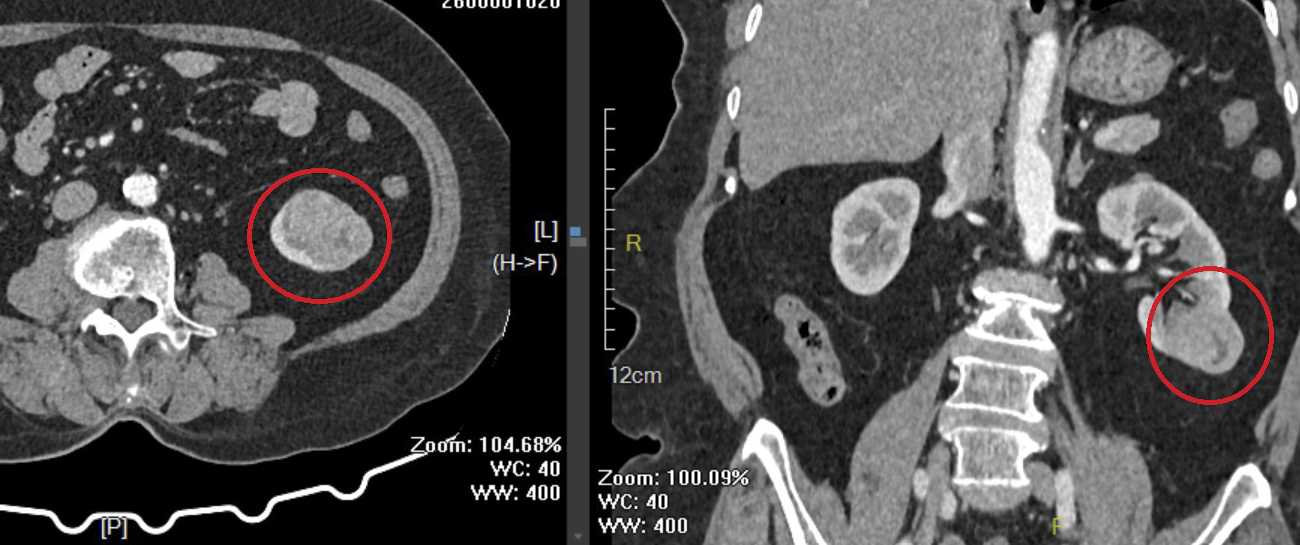

Hình ảnh khối u thận trái của người bệnh B. qua phim chụp cắt lớp vi tính.

Thời gian qua, khoa Ngoại tổng hợp, Bệnh viện Đa khoa Trung ương Quảng Nam đã tiếp nhận và điều trị nhiều trường hợp ung thư được phát hiện trong những tình huống hết sức bất ngờ. Điển hình là trường hợp người bệnh nữ P.T.B. (76 tuổi, trú xã Vạn Tường, tỉnh Quảng Ngãi) tình cờ phát hiện khối u thận trái trong quá trình nhập viện phẫu thuật viêm ruột thừa. Trước đó, người bệnh hoàn toàn không có triệu chứng lâm sàng rõ ràng hay dấu hiệu đặc hiệu liên quan đến bệnh lý ung thư.

Sau khi được tư vấn và thăm khám kỹ lưỡng, các bác sĩ đã thống nhất chỉ định phẫu thuật nội soi cắt một phần thận trái chứa khối u, đồng thời bảo tồn tối đa phần nhu mô thận lành. Ca phẫu thuật diễn ra thuận lợi, người bệnh hồi phục tốt sau mổ, sức khỏe ổn định và đã được xuất viện vào ngày 26/01/2026.

Hình ảnh khối u có kích thước 3x4x3cm sau phẫu thuật.